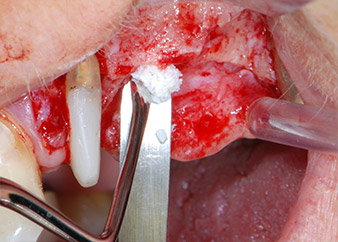

Prior to implant placement, and following verification of an intact Schneiderian membrane (Fig. 9), the internal sinus floor was augmented at both implant sites by means of xenogeneic bone substitute material (Bio-Oss, Geistlich Biomaterials) (Fig. 10).

The implants (Restore, Keystone Dental, diameter 3,75 mm, length 8.0 mm) were placed with the implant motor

(Figs. 11 and 12).